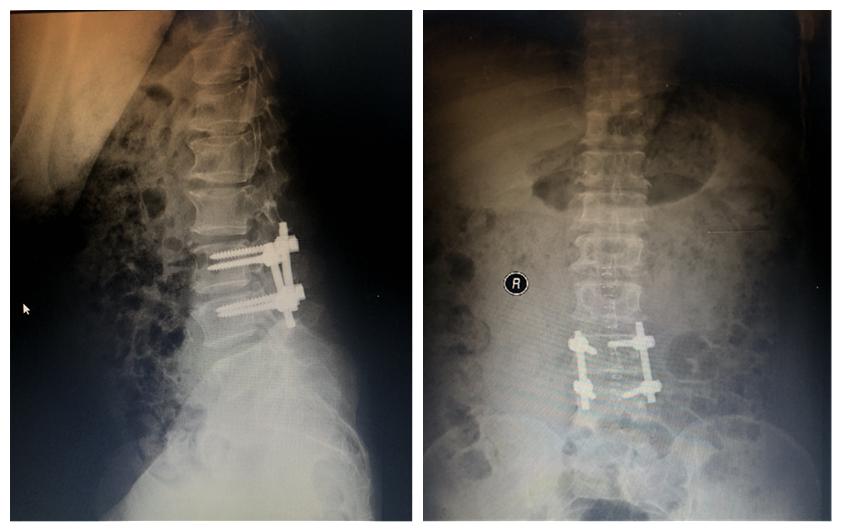

患者王先生,45岁,近日出现左髋部酸钝性疼痛,疼痛可放射至左膝盖,伴有左下肢活动受阻,无法站立,口服药物后症状无明显缓解,遂来我院急诊创伤外科就诊。经过相关检查后发现患者腰椎间盘突出(L3/4脱出),向上游离到上位椎体中部。患者临床症状明显,保守治疗效果不理想,与患者及家属沟通后,副主任医师张显、主治医师王久清等治疗组经过严谨的术前讨论,决定为患者行L3/4间盘摘除、椎管减压术。术中可见L3左侧椎间孔处一处肿物压迫腰3神经根及硬膜囊,治疗组顺利完整取出肿物。术后患者恢复良好,现已康复出院。